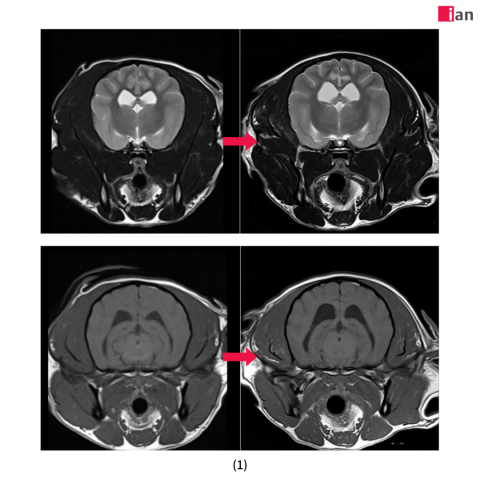

2023년 말 최첨단 AI MRI 소프트웨어를 도입한 이안동물의학센터는 촬영 시간 단축과 영상 품질 극대화라는 두 마리 토끼를 동시에 잡았다. 딥러닝 알고리즘을 통한 이미지 재구성과 노이즈 제거, 선명도 향상은 보다 신속하고 정확한 진단을 가능하게 했으며, 보호자와 반려동물 모두에게 높은 만족도를 제공하고 있다.

특히 AI 소프트웨어 도입 이후 촬영 시간이 기존 대비 최대 절반으로 줄어드는 등 검사 효율성이 크게 향상됐다. 이는 보호자들의 시간적 부담을 덜어줄 뿐 아니라 환자의 마취 시간 단축으로 검사 안전성을 더욱 높이는 효과를 가져왔다. 또한 이미지 퀄리티 향상으로 정밀한 판독이 가능해져 질병의 조기 발견과 정확한 진단을 통한 치료 전략 수립에 커다란 진전을 이뤄냈다. 여기에 이안동물의학센터 전담 마취팀의 철저한 관리까지 더해져 반려동물 검사 전 과정에서 신뢰도 높은 의료 서비스를 제공하고 있다.